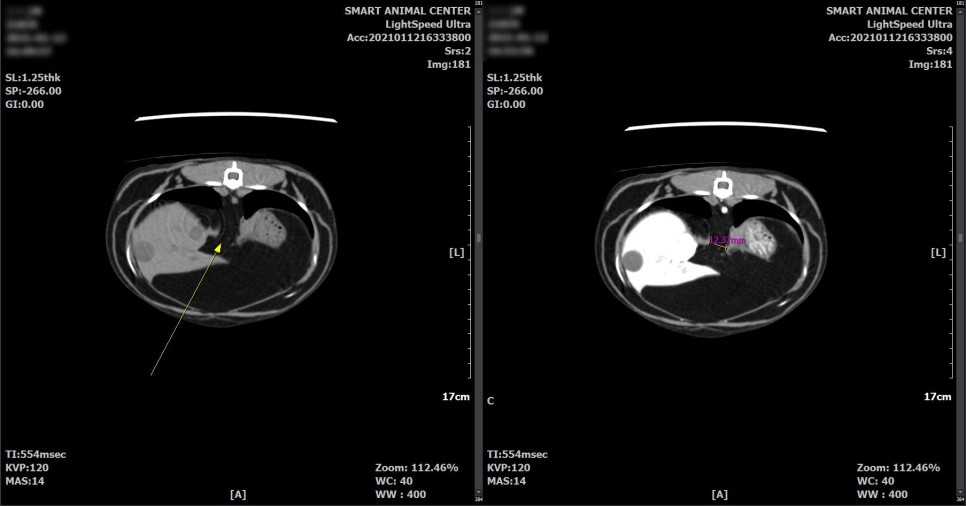

보다 면밀한 흉부 평가를 위해서 CT촬영을 실시했습니다.

CT 검사 결과

횡격막의 일부 결손 부위와 흉강 내 다량의 지방 병변이 확인되었습니다.

횡격막 결손부에 의한 다량의 지방 디스크가 있을 수 있으며,

또한 영상학적으로 악성도를 지시하는 것과 같은 소견은 관찰되지 않았습니다.

다량의 지방으로 폐 실질 등, 왼쪽 변위가 유발되고 있다고 판단되었습니다.